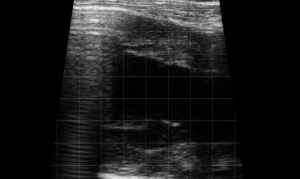

SIMON Ultrasound Database

This ultrasound database is a free resource for students and doctors!

Our collection includes videos of dogs, cats, horses, cows, humans, and many other species!